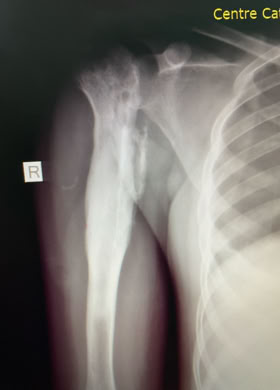

Traumatología

Coste del material de Osteósíntesis para una fractura de fémur

Gracias a COEM es posible realizar una traumatología del siglo XXI en una comunidad que de otra forma solo tendría acceso a una medicina medieval